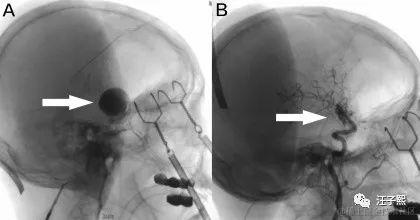

我见没有达到目的,换了一个角度继续问,“Z医生,从我前天拍的核磁共振检查报告来看,明天的手术,切除肿瘤难度大吗? ” 出乎我意料,这次Z医生没有给出诸如“有一定的难度”这样的答复,而是给我讲述了一些常识。放射科出具的核磁共振检查报告结果,就是病人拿给外科大夫看的那一张张黑乎乎的塑料片子,到底是怎么生成的呢?这要从我们是如何进行核磁共振检查说起。

参加核磁共振检查的人,会平躺在一个装置上(有点像电影《普罗米修斯》里女主伊丽莎白-肖博士进行剖腹手术,取出自己体内异形使用的手术仓),这套装置会产生一个特殊的磁场,并发出无线电射频脉冲激发人体内的氢原子核,引起氢原子核共振,并吸收能量。在停止射频脉冲后,氢原子核按特定频率发出射电信号,并将吸收的能量释放出来,被检查装置的接受器收录,通过计算机处理生成图像,这就是做核磁共振成像的一个完整流程。

Z医生告诉我,“你三天前的核磁共振片子结果,仅仅是你当时颅内的一个二维投影,我们可以用来作为参考进行手术难度评估,但它不是评估手术难度的决定性依据。一切都只能到了手术中,进入颅内看到实时情况,才能准确下结论。 ” 我心想,嗯嗯,我明白,核磁共振其实就是颅内实时状态,在某个时间点上给它做的一个镜像(snapshot), 这个镜像把颅内状况从3维降成了2维,根据该镜像无法逆向还原制作镜像那个时间点内的颅内状况。